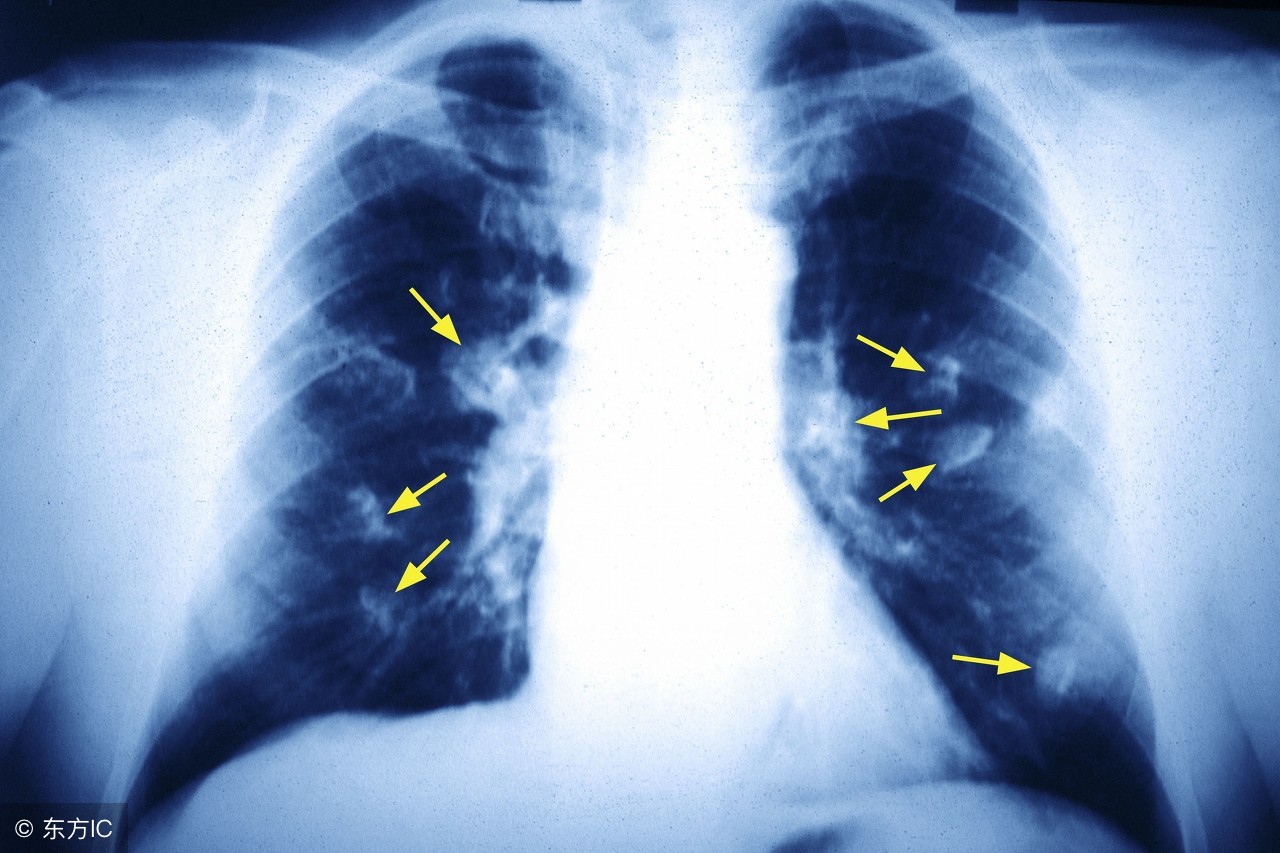

随着社会的发展,人们生活水平的在不断的提升,但是通过调查得出患有肺癌的人数也在不断的增加,肺癌让患者受到了很严重的痛苦,相信大家都想知道,究竟肺癌更倾向于哪类人呢?

我们要记住3个“20”,吸烟20年以上的,20岁以下开始吸烟的,每天吸烟20支以上的。3个“20”里,只要有一条,都属于肺癌高危人群。而每天吸烟2包以上、烟龄超过40年的“老烟枪”自然要属于肺癌高危人群了。

医学统计表明,每日吸烟25支以上者的肺癌发病率为250/10万,这个是很常见的容易患肺癌的人群。未吸烟者的肺癌发病率为10/l0万,如果他们之间的其他生活、工作条件相似,那么,每日吸烟25支者的肺癌发病率是未吸烟者的25倍,“25”这个数字就是每日吸烟25支以上者肺癌发病的相对危险度。

肺癌高危人群就是指肺癌发病率高、肺癌相对危险度高的一部分人。